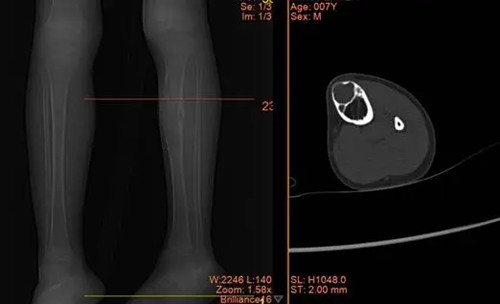

骨科三病区闫鹏主任、樊彦伟副主任,是经验丰富、医术精湛的专家,热情地接待了他们,经过详细的询问病史,仔细地查体,结合影像学及实验室检查,诊断为:左胫骨骨肿瘤(非骨化性纤维瘤/骨巨细胞瘤/纤维性骨皮质缺损/内生软骨瘤/骨囊肿?) ,考虑左胫骨非骨化性纤维瘤可能性大。

X线可见:长骨骨干处的偏心性、多房性骨质破坏区,边界清楚。

病变区多呈圆形或椭圆形,长轴与骨干平行。

周围可有轻度硬化边,无骨膜反应。

CT 能更清晰地显示骨质破坏的范围、程度和内部结构。病变区呈低密度,边缘可有硬化,内部可见分隔。

MRI 在 T1 加权像上呈低或中等信号,T2 加权像上信号多样,可呈低、中等或高信号,取决于肿瘤内的组织成分。边缘可有低信号的硬化带。